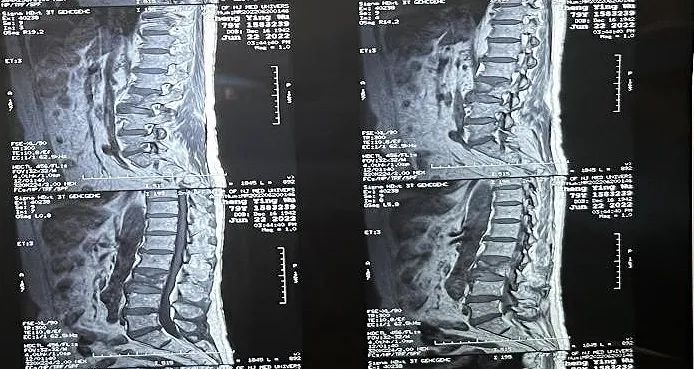

術(shù)中切口5毫米,在大平板C臂機(jī)的透視指引下,確定了進(jìn)針的方向及進(jìn)針的深度。經(jīng)椎弓根向椎體置管,建立通道,插入骨擴(kuò)張器(球囊)。球囊擴(kuò)張恢復(fù)椎體高度,并在椎體內(nèi)形成空腔,確定骨水泥的注入劑量,并注入骨水泥觀察其擴(kuò)散情況。

球囊擴(kuò)張示意圖